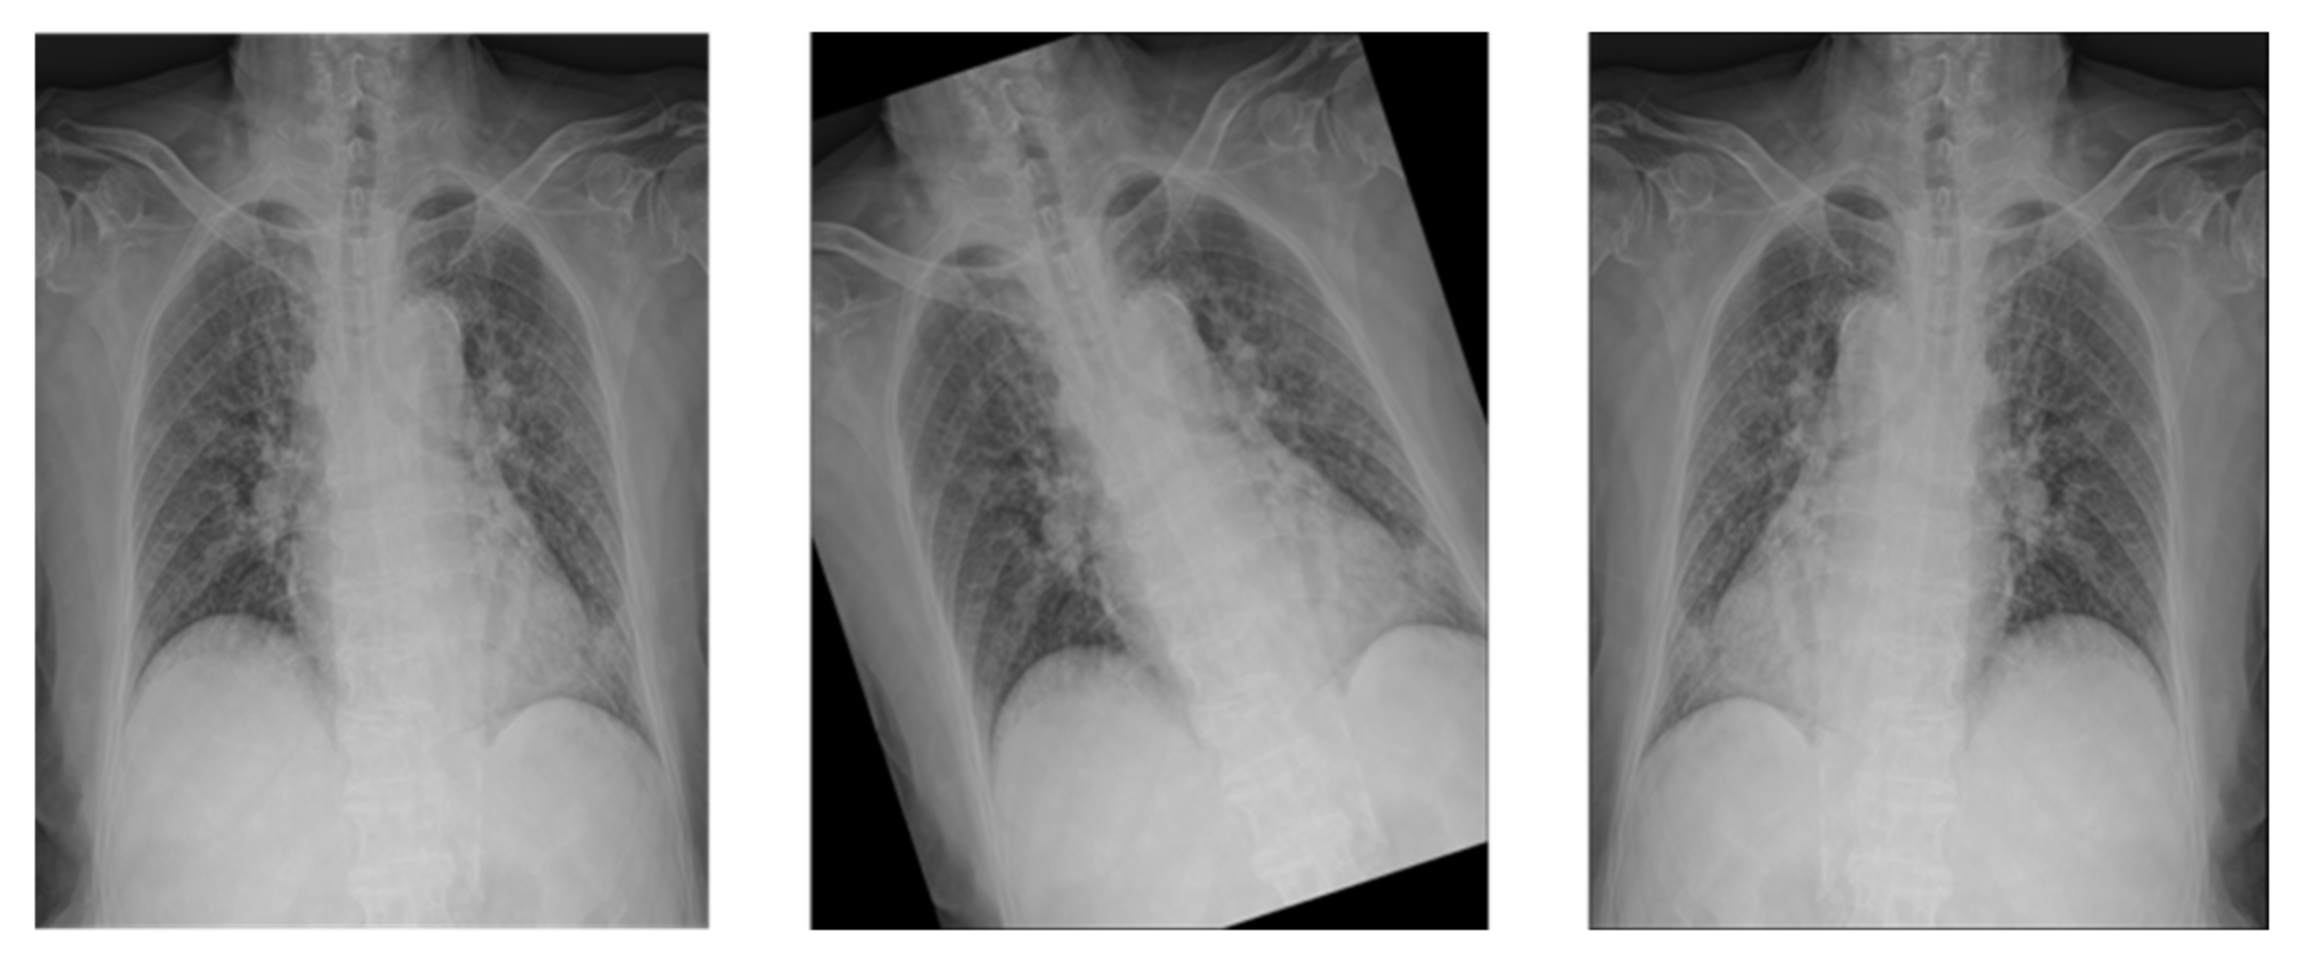

To prevent overfitting and improve performance, Rand Augment [21] was used for data augmentation. Rand Augment is an augmentation that applies up to N random augments with a maximum random intensity of M.

In this study, Augments such as FlipLR, Identity, AutoContrast, Equalize, Rotate, Solarize, Color, Posterize, Contrast, Brightness, Sharpness, ShearX, ShearY, TranslateX, TranslateY were applied. The maximum number N is 2, and the maximum intensity M is set to 28, as shown in Figure 10.

Since deep learning approach is a data-driven approach, the more training data we have, the higher performance we would achieve. Therefore, we did the augmentation in order to increase the number of training sets. By applying Rand augmentation, number of augmented data was randomly created up to maximum 2.

Figure 10. X-ray image with Rand Augment applied.